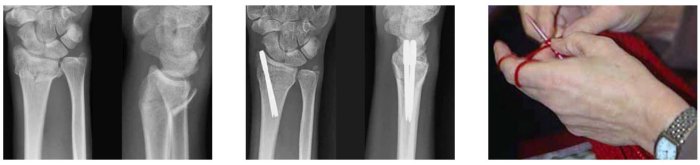

In this case, we see the preoperative radiographs of a 70-year-old, independent woman with medical comorbidities.

Stability was achieved under local MAC, utilizing minimally invasive T-Pin fixation.